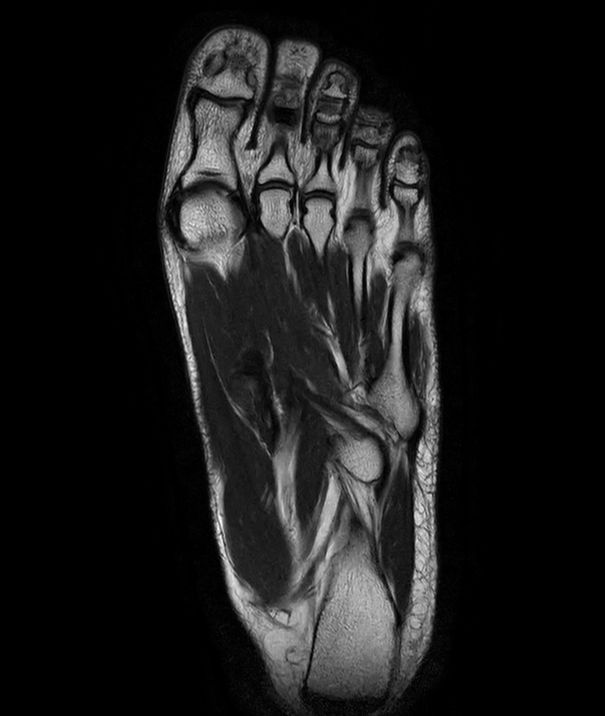

SmartSpeed Forefoot imaging

Suzukake Central Hospital, Japan

This forefoot ExamCard includes 3 orientations and several different contrasts. SmartSpeed is used to increase imaging speed while delivering outstanding image quality.

Sagittal T2w TSE

-

Sagittal T1w TSE

Sagittal STIR TSE

Coronal T2w TSE